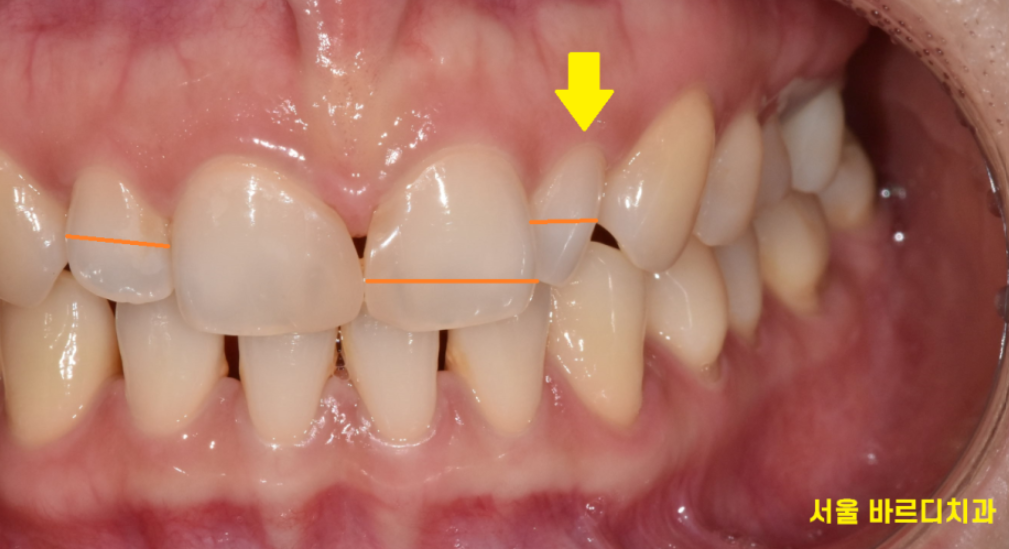

환자분은 바로 옆 대문니가 크다 보니

치아가 각도상 비틀어져 있어서

유독 작게 보이네요.

반대편 같은 치아의 경우 각도는 제대로 되었지만

이 역시 왜소치에 속합니다.